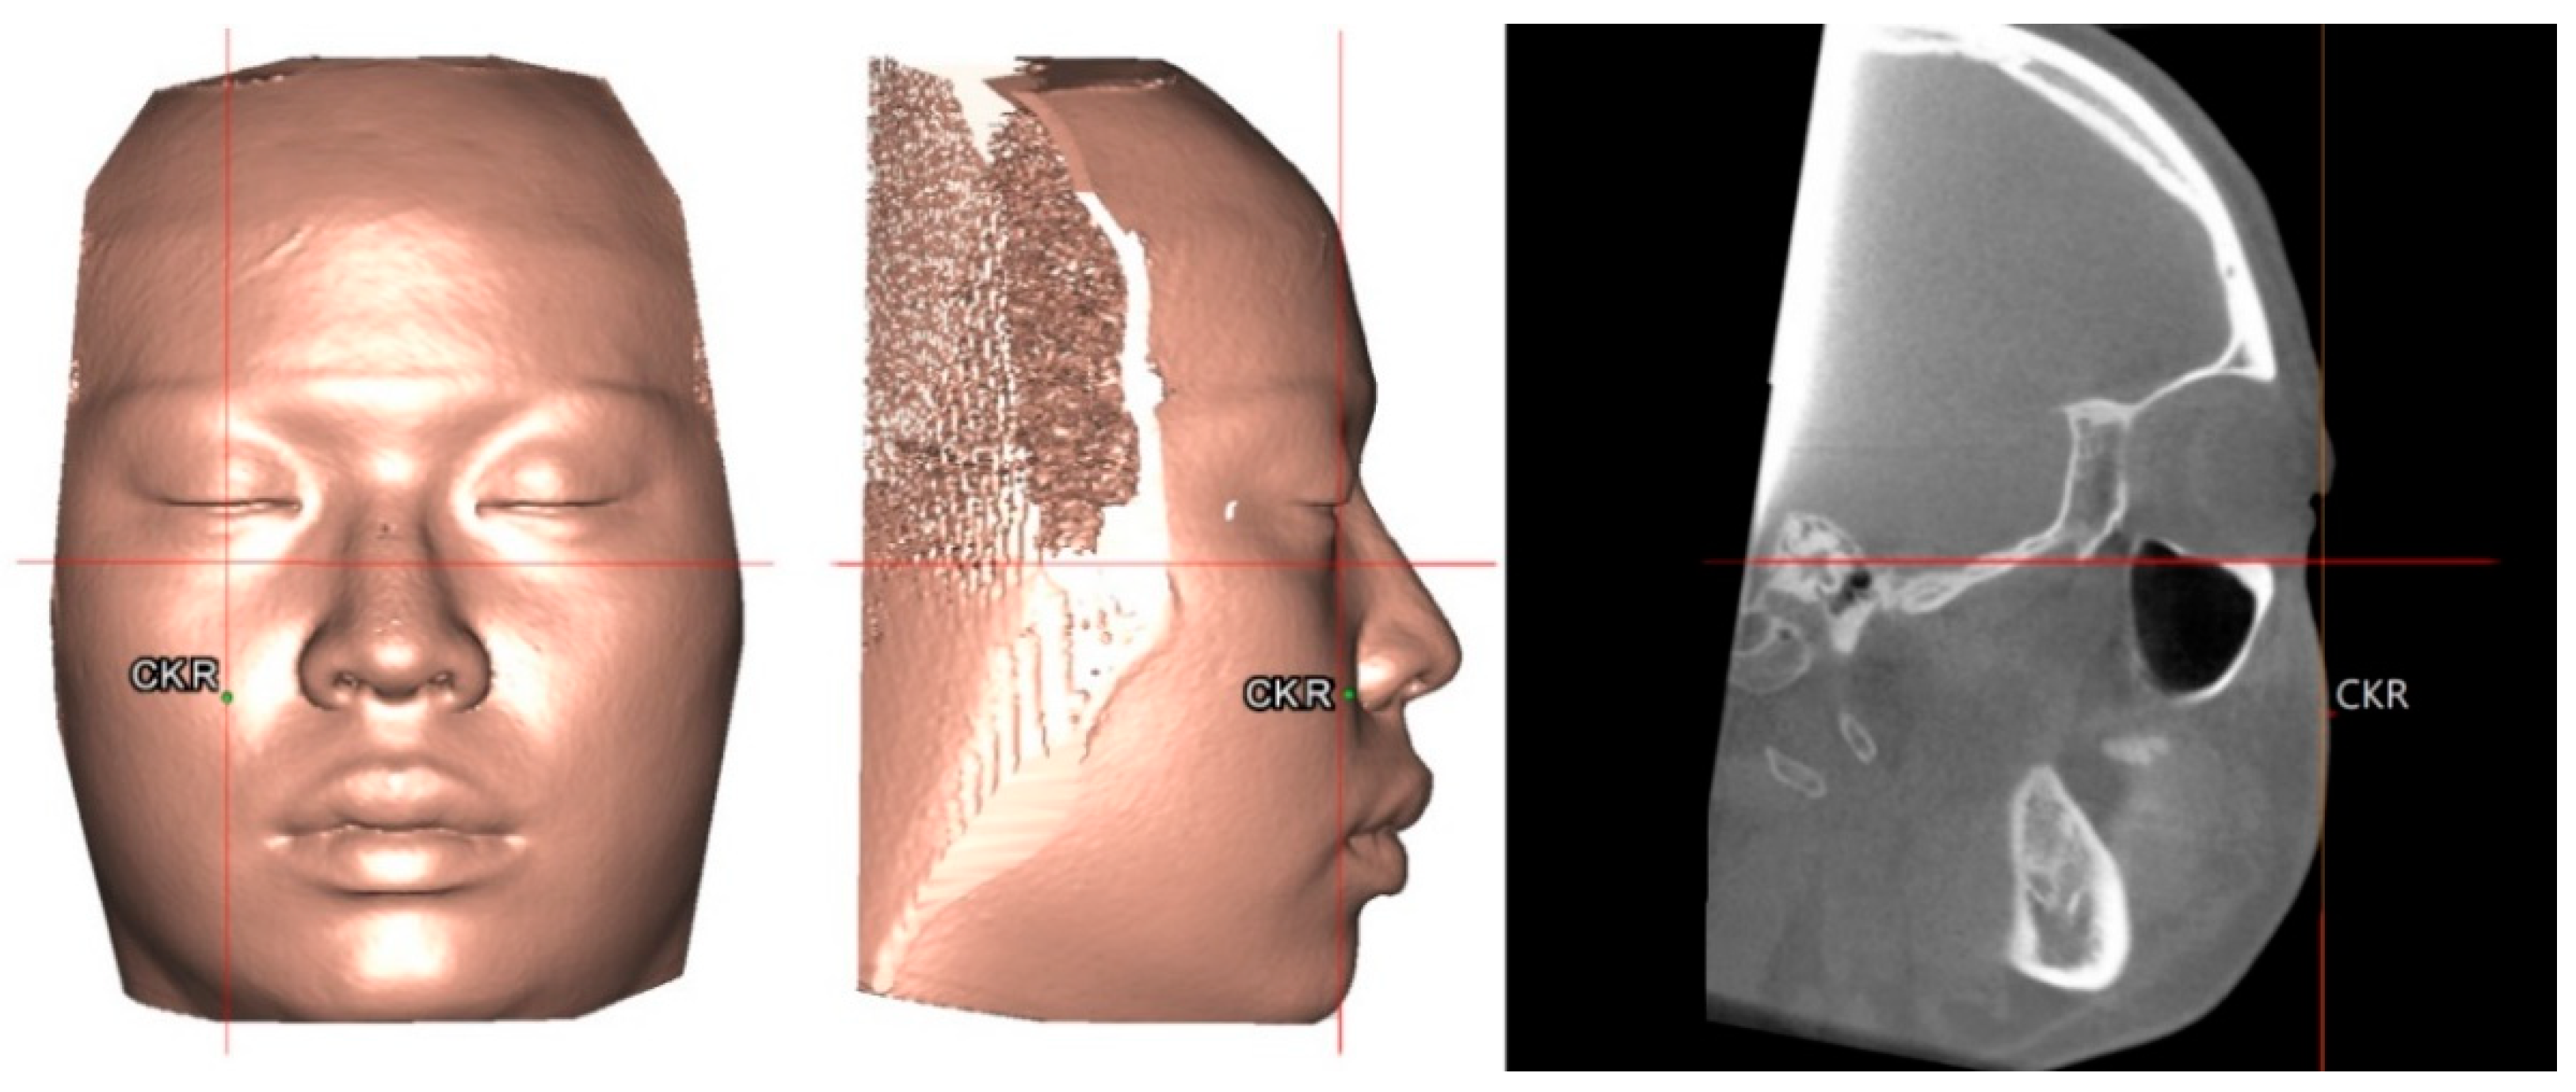

3.5. Outcome of Computer-Assisted Simulation

Figure 6. Practical example of the 3D surgical simulation based on 3D norms for orthognathic surgery treatment using the single-splint, two-jaw surgery technique. Skeletal Class III deformity (left) before and (right) after computer-aided simulation. After setting the planned final occlusion setup by mobilization of osteotomized distal mandible segment in direction to the fixed maxilla, the maxillomandibular complex (MMC; composed by Le Fort I and distal mandible segments) was moved as a single unit in 6 degrees of freedom (including translational and rotational directions) to meet the normal position of point A to N vertical line, angle of convexity, Pog, vertical ratio, and symmetry. Pitch clockwise rotation of MMC was needed to fit the best facial convexity and obtain a better smile arc. The final modifications were decided by the surgeon and orthodontist according to the clinical evaluation of the soft tissue facial profile. For definitions, please, refer to Table 1 and Table 2.